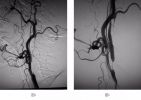

【首例病例】重症医学科独立完成颈内动脉支架植入术

2014年10月11日,我院重症医学科的神经介入独立完成一例颈内动脉闭塞取栓再通后支架成形术,患者为男性,62岁,突发左侧肢体瘫痪,语言障碍,神志清楚,医生初步诊断后认为颈内动脉闭塞,发病时间短,来院及时,正是治疗的好时机,错过就可能危及生...